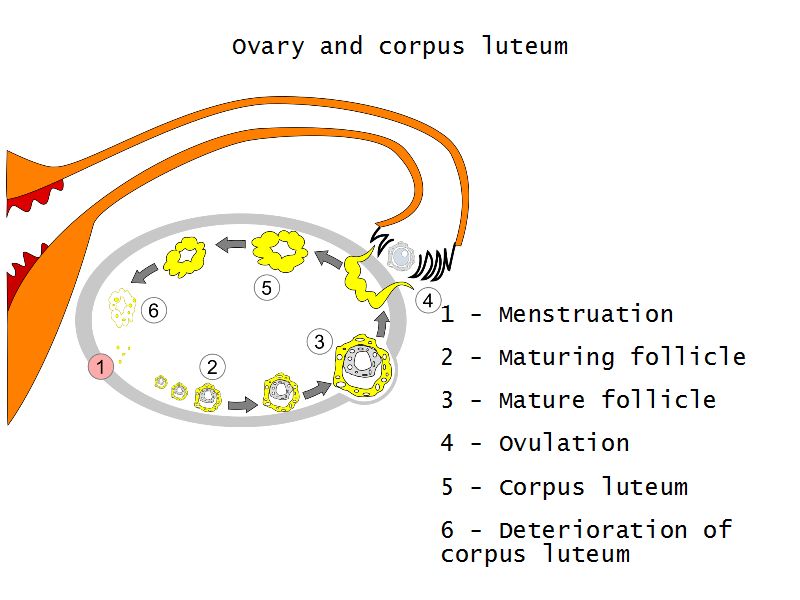

Follicular maturation

- Primordial follicle

- Growing follicle

- Primary follicle

- Secondary follicle

- Mature follicle (Graafian)

Components of a follicle

- Theca

- externa

- interna

- basal lamina

- Granulosa cells

- Antrum

- Cumulus oophorus >> Corona radiata

- Oocyte

Corpus luteum

Slide 91

Corpus luteum

- Two major cell types

- Granulosa lutein cells

- modified granulosa cells

- Theca lutein cells

- modified theca interna cells

- Many capillaries

Menstrual cycle

- Follicular phase

- Luteal phase

- Menstrual phase